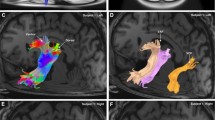

In this work, we also present the virtual dissection of the left hemisphere IFOF of a single subject. Figure 13 displays the whole IFOF with all subcomponents color-coded in the same way as they are depicted in Figs. 14 (superficial component) and 15 (deep component). Figure 14 displays the superficial component as defined by the part of the IFOF directed to the IFG. Figure 15 displays the IFOF without the superficial component.

In this picture all subcomponents color-coded of IFOF are shown with DTI. The superficial layer of IFOF bundle is displayed in red color and the three portions of deep layer, posterior, middle and anterior are colored in green, orange and blue, respectively. a axial view; b sagittal view; c coronal view

DTI reconstruction of the deep layer after removal of the superficial layer. The anterior component is displayed in blue, the middle in orange and the posterior one in green. The DTI results confirm, once again, the course and terminations territories demonstrated in the cadavers dissections. a axial view; b sagittal view; c coronal view

To simplify the description of DTI results, we will assume a postero-anterior course of the IFOF with a posterior origin and an anterior termination. Similarly to what described by Lawes et al. (2008), we found three main apparent origins of the IFOF located in the occipital inferior gyrus, in inferior portion of the occipital middle gyrus and to a minimal extent within the lingual gyrus. Within the occipital inferior gyrus, it is possible to identify two apparently separate stems: one located in the most anterior and lateral part at the border with the inferior temporal gyrus, the other located in a more medial and posterior region at the border with the fusiform gyrus. From these regions the streamlines follow a path that closely resemble the one described in the anatomical dissection both in the paper by Lawes et al. (2008) and in that of Martino et al. (2009). Streamlines converge and pass through the extreme capsule where the whole tract appears to be compacted. The terminations of the streamlines at the frontal lobe closely match the ones previously described in the anatomical dissection, i.e., they reach four distinct areas: the IFG, the lateral OFC, the medial portion of the MFG and the posterior portion of the DLPFC. Based on the anatomical dissection results, we selected the part of IFOF terminating in the IFG to verify its course and location (Fig. 14a–c). This part should correspond to what, based on the anatomical dissection, has been labeled as the superficial portion. We found that it originates from the antero-lateral portion of the occipital inferior gyrus and from the antero-inferior portion of the occipital middle gyrus with a minimal component originating from the lingual gyrus. After passing in the most inferior and lateral portion of the extreme capsule, it turns lateral to terminate in the IFG, closely resembling the anatomical dissection path. Once this superficial component was removed, it was possible to explore the remaining part of the IFOF that should match the deep portion as described in the anatomical dissection (Fig. 15a–c). Notably, immediately after passing through the extreme capsule, where it appears located medially and superiorly to the superficial portion (Fig. 13a–c), it divides into three fan-shaped clusters of streamlines directed, respectively, to the lateral OFC, to the MFG and to the DLPFC (Fig. 15a–c). Following backwards the occipital origin of these three bundles, we found that orbito-frontal part originates mostly from the medial posterior portion of the inferior occipital gyrus at the border with the fusiform gyrus with few streamlines coming from the postero-lateral stem in the inferior occipital gyrus. The other two bundles of streamlines directed to the MFG and to the DLPFC apparently originate almost only from the stem located in the antero-lateral portion of the inferior occipital gyrus at the border with the posterior part of the inferior temporal gyrus.